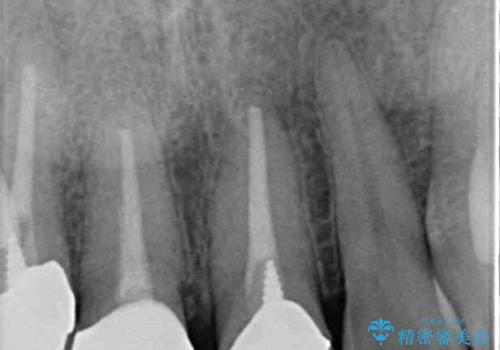

- 前歯の変色した歯を治したいことを主訴として来院された患者様です。

数年前、外傷により両隣の歯とともに根管治療を行い、その後両隣の歯はオールセラミッククラウンにて補綴したそうです。

時間の経過とともに、セラミックにしなかった当該歯の変色が目立つようになり、オールセラミッククラウンにて補綴することとしました。